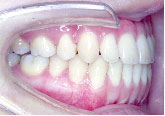

20代女性 受け口とあごのずれが気になり来院

下の歯が上の歯より前に出て前歯は咬めていません。左上の第2小臼歯は骨の中に埋まっています。

また下あごは左にずれています。顎変形症、下顎前突と診断しました。